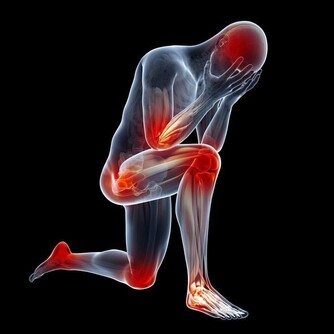

苗大姐坐在陽台上曬著太陽,她把雙手放在膝蓋上仔細看著,關節似乎有些變形,摸起來硬硬的,她想起來今早起床的時候手指有點不對勁,有點彎曲不了,就像被膠水粘住了,活動了很久才舒展開來。自己今年才51歲,按道理來說不老啊,這到底是怎麼了?

大家不禁奇怪,為啥好好的手指關節疼呢?是因為老了嗎?而且出現這種症狀的多是女性患者,還有一定的年齡特徵,大都是在五十歲上下,有不少患者已經絕經了,和它有關嗎?今天就來帶大家看看,手指僵硬、疼痛動不了是咋回事。

手指僵硬、疼痛動不了或是4種原因

開頭我們就說了,來者大多是中年女性,這就不得不考慮性別和年齡兩個重要因素,我們自然而然會想到絕經和更年期。45-55之間的女性,逐漸發胖、衰老,體內的鈣質流失,關節負擔越來越重,出現了病理性改變,其實,不僅是手指,患者的膝蓋、肩膀、腰椎都可能受此影響。